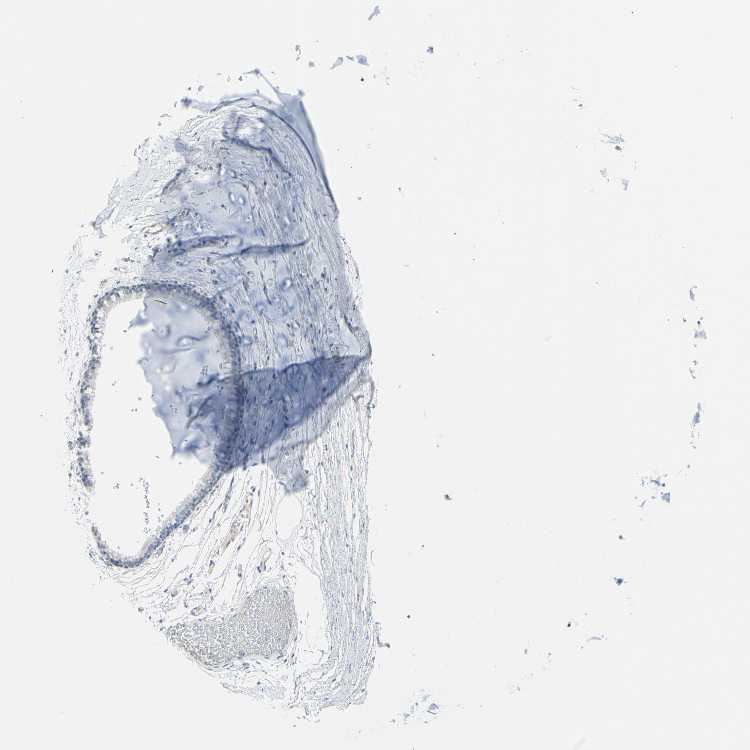

SOFT TISSUE 1 - Antibody stainingi

Antibody staining in the annotated cell types in the current human tissue is reported as not detected, low, medium, or high, based on conventional immunohistochemistry profiling in selected tissues. This score is based on the combination of the staining intensity and fraction of stained cells.

Each image is clickable and will lead to virtual microscopy that enables deeper exploration of all samples and also displays staining intensity scores, fraction scores and subcellular localization as well as patient and tissue information for each sample.

Antibody HPA049158Antibody HPA070525Antibody CAB010142

Chondrocytes Not detectedNot detectedNot detected

Fibroblasts Not detectedNot detectedNot detected

Peripheral nerve Not detectedNot detectedNot detected